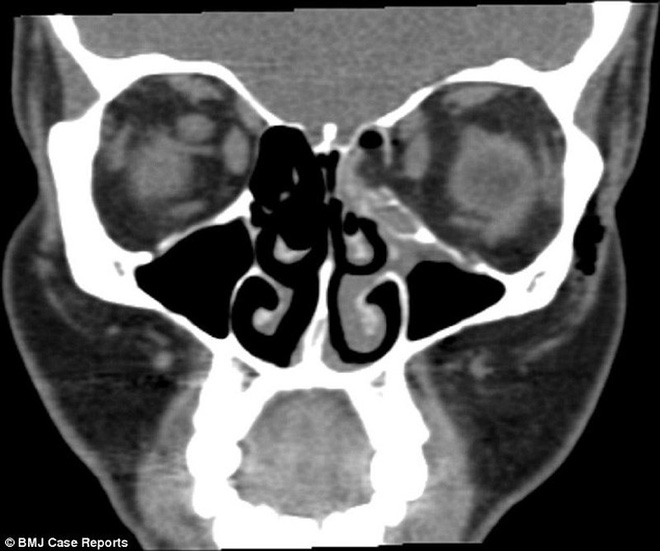

Thông thường, các bác sĩ cho hay, xương mũi chỉ có thể vỡ nếu bị đấm một cú thật mạnh. Thế nhưng, chưa ai từng nghe xương mũi bị gãy là do hỉ mũi quá mạnh cả. Tình huống hy hữu này đã khiến bệnh nhân chịu nhiều tổn thương.

Phim chụp CT cho thấy bệnh nhân đã bị gãy một xương trong hốc mắt vì áp lực trong xoang quá cao khi hỉ mũi. Vết vỡ làm mỡ tràn vào đường hô hấp, khí bị kẹt trong mô quanh mắt.

Vỡ xương hốc mắt thường xảy ra khi có va đập với mặt. Trường hợp thương tích do hỉ mũi khá hiếm. Người phụ nữ này cũng hút hơn 20 điếu thuốc mỗi ngày, có thể điều này đã gây thay đổi về áp lực trong xoang.